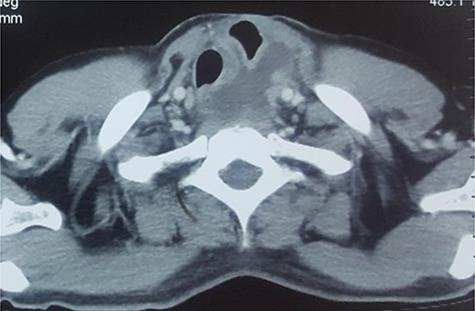

Mucocele of the native esophagus is a rare complication after esophageal bypass surgery for various indications. Esophageal mucoceles rarely get infected, forming a 'pyocele' which becomes symptomatic. Various approaches have been utilized in the management of such pyoceles. We report a similar patient managed successfully in our center utilizing a thoracoscopic deroofing and partial excision of the pyocele.

原生食管黏液囊肿是各种适应证食管旁路手术后罕见的并发症。食管黏液囊肿很少发生感染,形成有症状的“脓性囊肿”。在处理此类脓性囊肿时已采用了各种方法。我们报告了在我们中心成功治疗的一名类似患者,采用胸腔镜下脓性囊肿去顶和部分切除术。